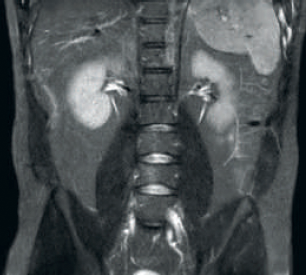

Result: Improved SNR and image resolution

Result: Noisy images using identical scan parameters

dStream RF receive technology digitizes the MR signal directly in the RF coil, resulting in an increase of up to 40% more SNR* throughout the whole image volume.